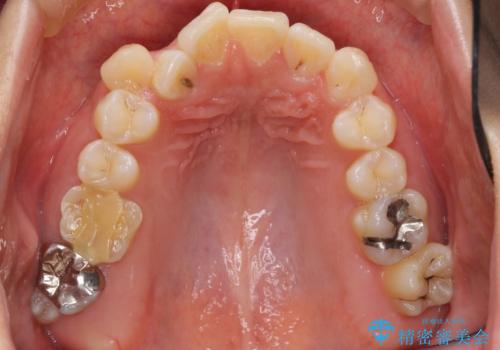

前歯のクロスバイト、上の前歯の正中が右にずれていました。

右上の奥歯の高さもない状態でしたが、矯正治療が終わってからしっかりかぶせました。

上下左右の小臼歯を抜歯しています。